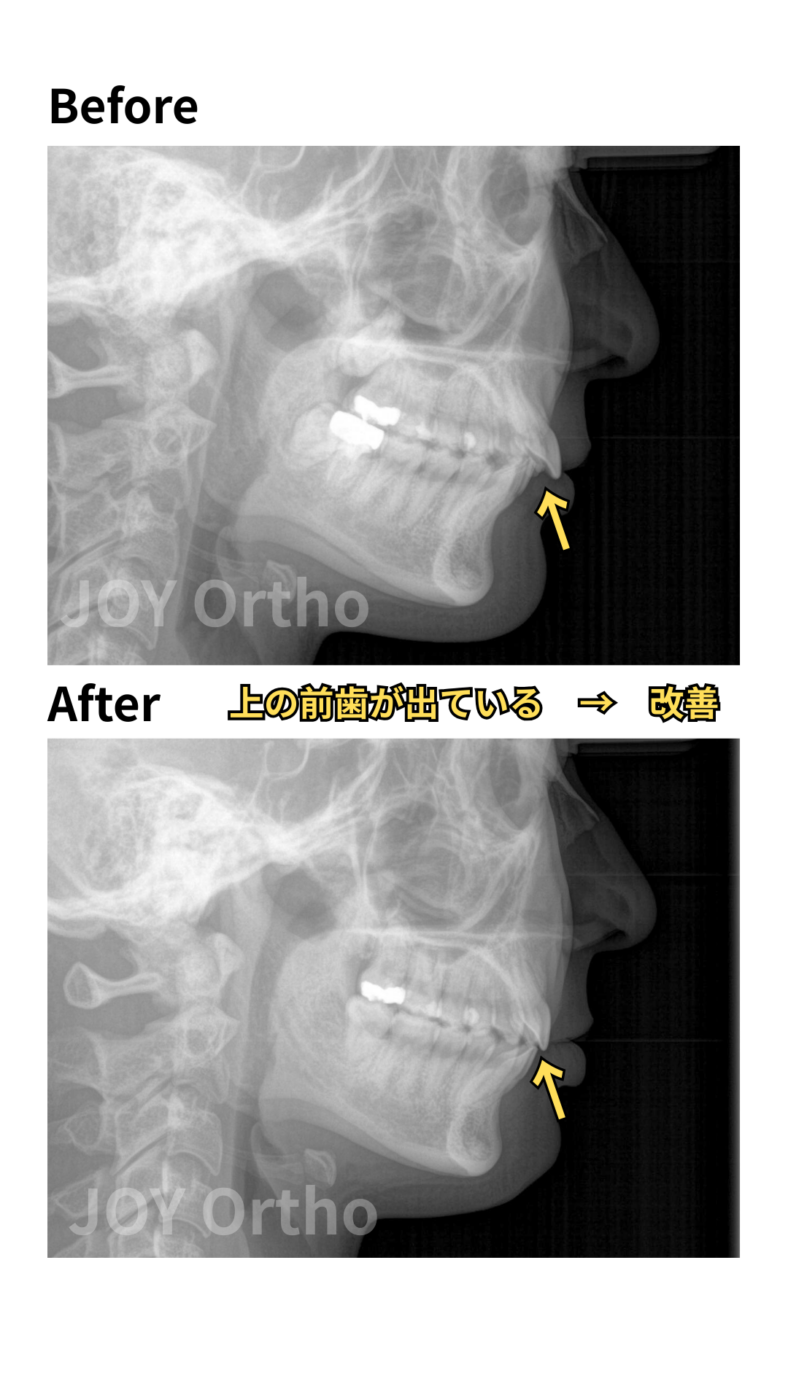

- 主訴:上の歯が出ている、一度、他院で矯正治療を行ったが、出っ歯が治らなかった。

- 診断名:上顎前突症、叢生

- 初診時年齢:25歳

- 治療に用いた主な装置:マルチブラケット装置、歯科矯正用アンカースクリュー

- 抜歯部位:上顎左右8番、右下8番、左下7番

- 動的治療期間・通院回数:2年3ヵ月・約30回

- 治療費概算:約100万円(税込、検査・診断料+矯正治療費+大臼歯加算+スクリュー費)+毎回の処置料3,300~5,500円(税込)

- リスクと副作用: 歯根吸収の可能性がある。大臼歯移動のため、通常より治療期間が延長する可能性が高い。

上顎前突が改善してきている。